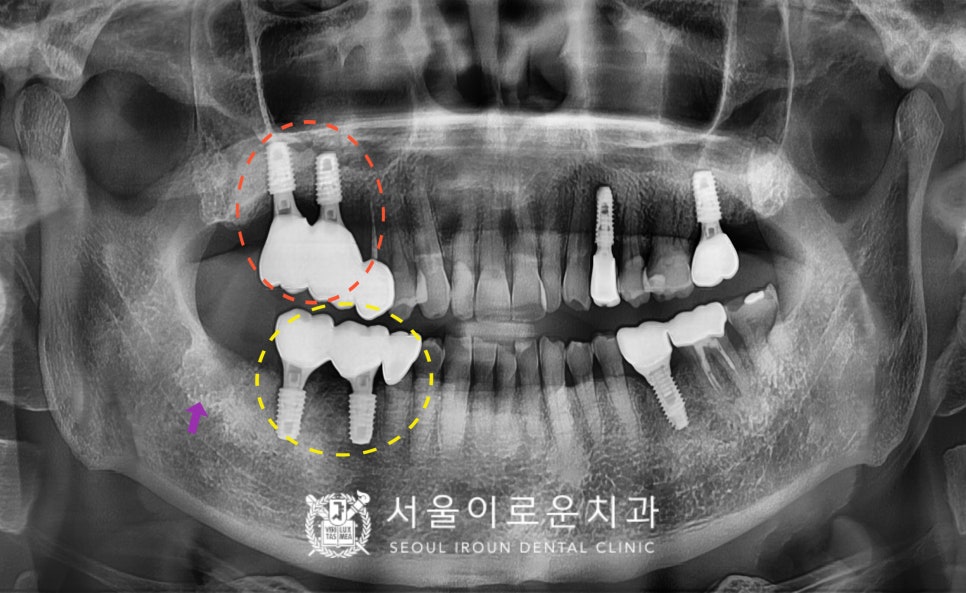

정밀한 검사를 위해

파노라마 사진을 촬영해

확인해 보았더니

노란색 동그라미의

기존 브릿지 보철물 치아 중

두 번째 큰 어금니(#47)가

충치로 인해 치아의 머리 부분과

뿌리가 분리가 된 상태였습니다..!

안타깝지만 살려 쓰기에는

예후가 좋지 않아

발치가 필요한 상황이었는데요.

다행히 두 번째 작은 어금니(#45)는

검진 시 특이 소견이 없어

크라운 치료를 진행하기로 하였답니다.

두 번째 큰 어금니(#47)는 발치하면서

동시에 어금니 자리에 임플란트 2개를

식립하기로 계획하였고,

바로 뒤의 사랑니(#48)도 함께

발치하기로 하였습니다.

그리고 오른쪽 위턱의 어금니는

상실된 상태로

임플란트를 같이 진행을 원하셨는데요.

상실 된 지 오래되어

뼈가 부족한 상황이라,

상악동 거상술을 동반한

임플란트 식립을 계획하였습니다. (2개 식립)